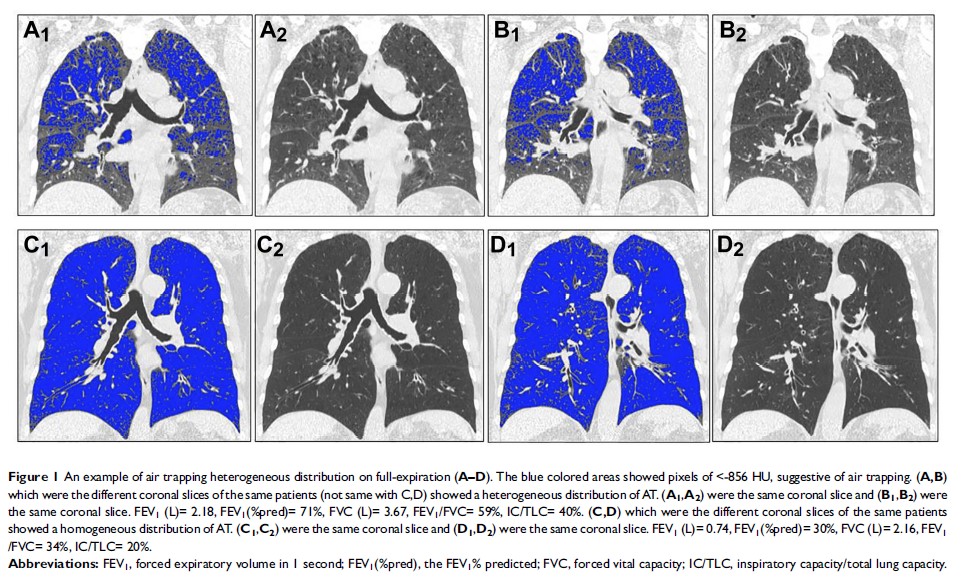

肺气肿和肺部空气滞积异质性对 COPD 患者肺功能的影响